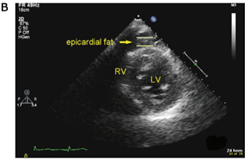

Η πρώτης γραμμής μέθοδος για τη μέτρηση του επικαρδίου λίπους είναι η δυσδιάστατη διαθωρακική ηχοκαρδιογραφία, που είναι μια ασφαλής, εύκολα αναπαραγώγιμη και μη επεμβατική μέθοδος που μπορεί να γίνεται τακτικά σε ασθενείς με υποψία καρδιαγγειακής νόσου ή κίνδυνο μεταβολικού συνδρόμου (εικόνα 3).

Εικόνα 3: Πάχος επικαρδιακού λίπους στο υπερηχοκαρδιογράφημα. Ορίζεται ως ο σχετικά ελεύθερος ήχου χώρος μεταξύ του εξωτερικού τοιχώματος του μυοκαρδίου και το σπλαχνικό στρώμα του περικαρδίου.

Ao: αορτή, LA: αριστερός κόλπος, LV: αριστερή κοιλία, RV: δεξιά κοιλία.

Παρά τα πλεονεκτήματα, το υπερηχοκαρδιογράφημα δεν είναι η βέλτιστη τεχνική για τον ποσοτικό προσδιορισμό του επικαρδιακού λίπου, αφού δεν μετρά τον συνολικό όγκο του.